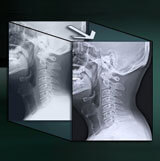

Applies edge enhancement and gray scale processing to multiple frequencies, improving visibility for varying densities and foreign structures. Useful in viewing spine, skull and orthopedic hardware images